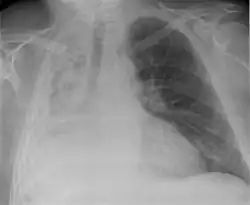

A pleural effusion is an accumulation of fluid inside the pleural space. If this collection of fluid gets large enough, it can also push structures in the chest away from it and cause a mediastinal shift. However, a pleural effusion can also pull the mediastinal structure towards itself. If this is the case, then there is an underlying condition causing the collapse of the lung on that side. An example is a tumor obstructing a bronchus and causing lung collapse and pleural effusion.[3]

Hemothorax

Hemothorax, or accumulation of blood in the pleural space, can result from trauma or surgical procedures in the chest. This accumulation of blood can grow large enough to compress the lung and push away other structures in the chest, thus causing a mediastinal shift.[6] On a chest x-ray, a hemothorax can appear similarly to a pleural effusion with blunting of the pleural recess and white out of normal lung zones.[7] In the setting of traumatic chest injury, rib fractures are also commonly observed on x-ray.[8]